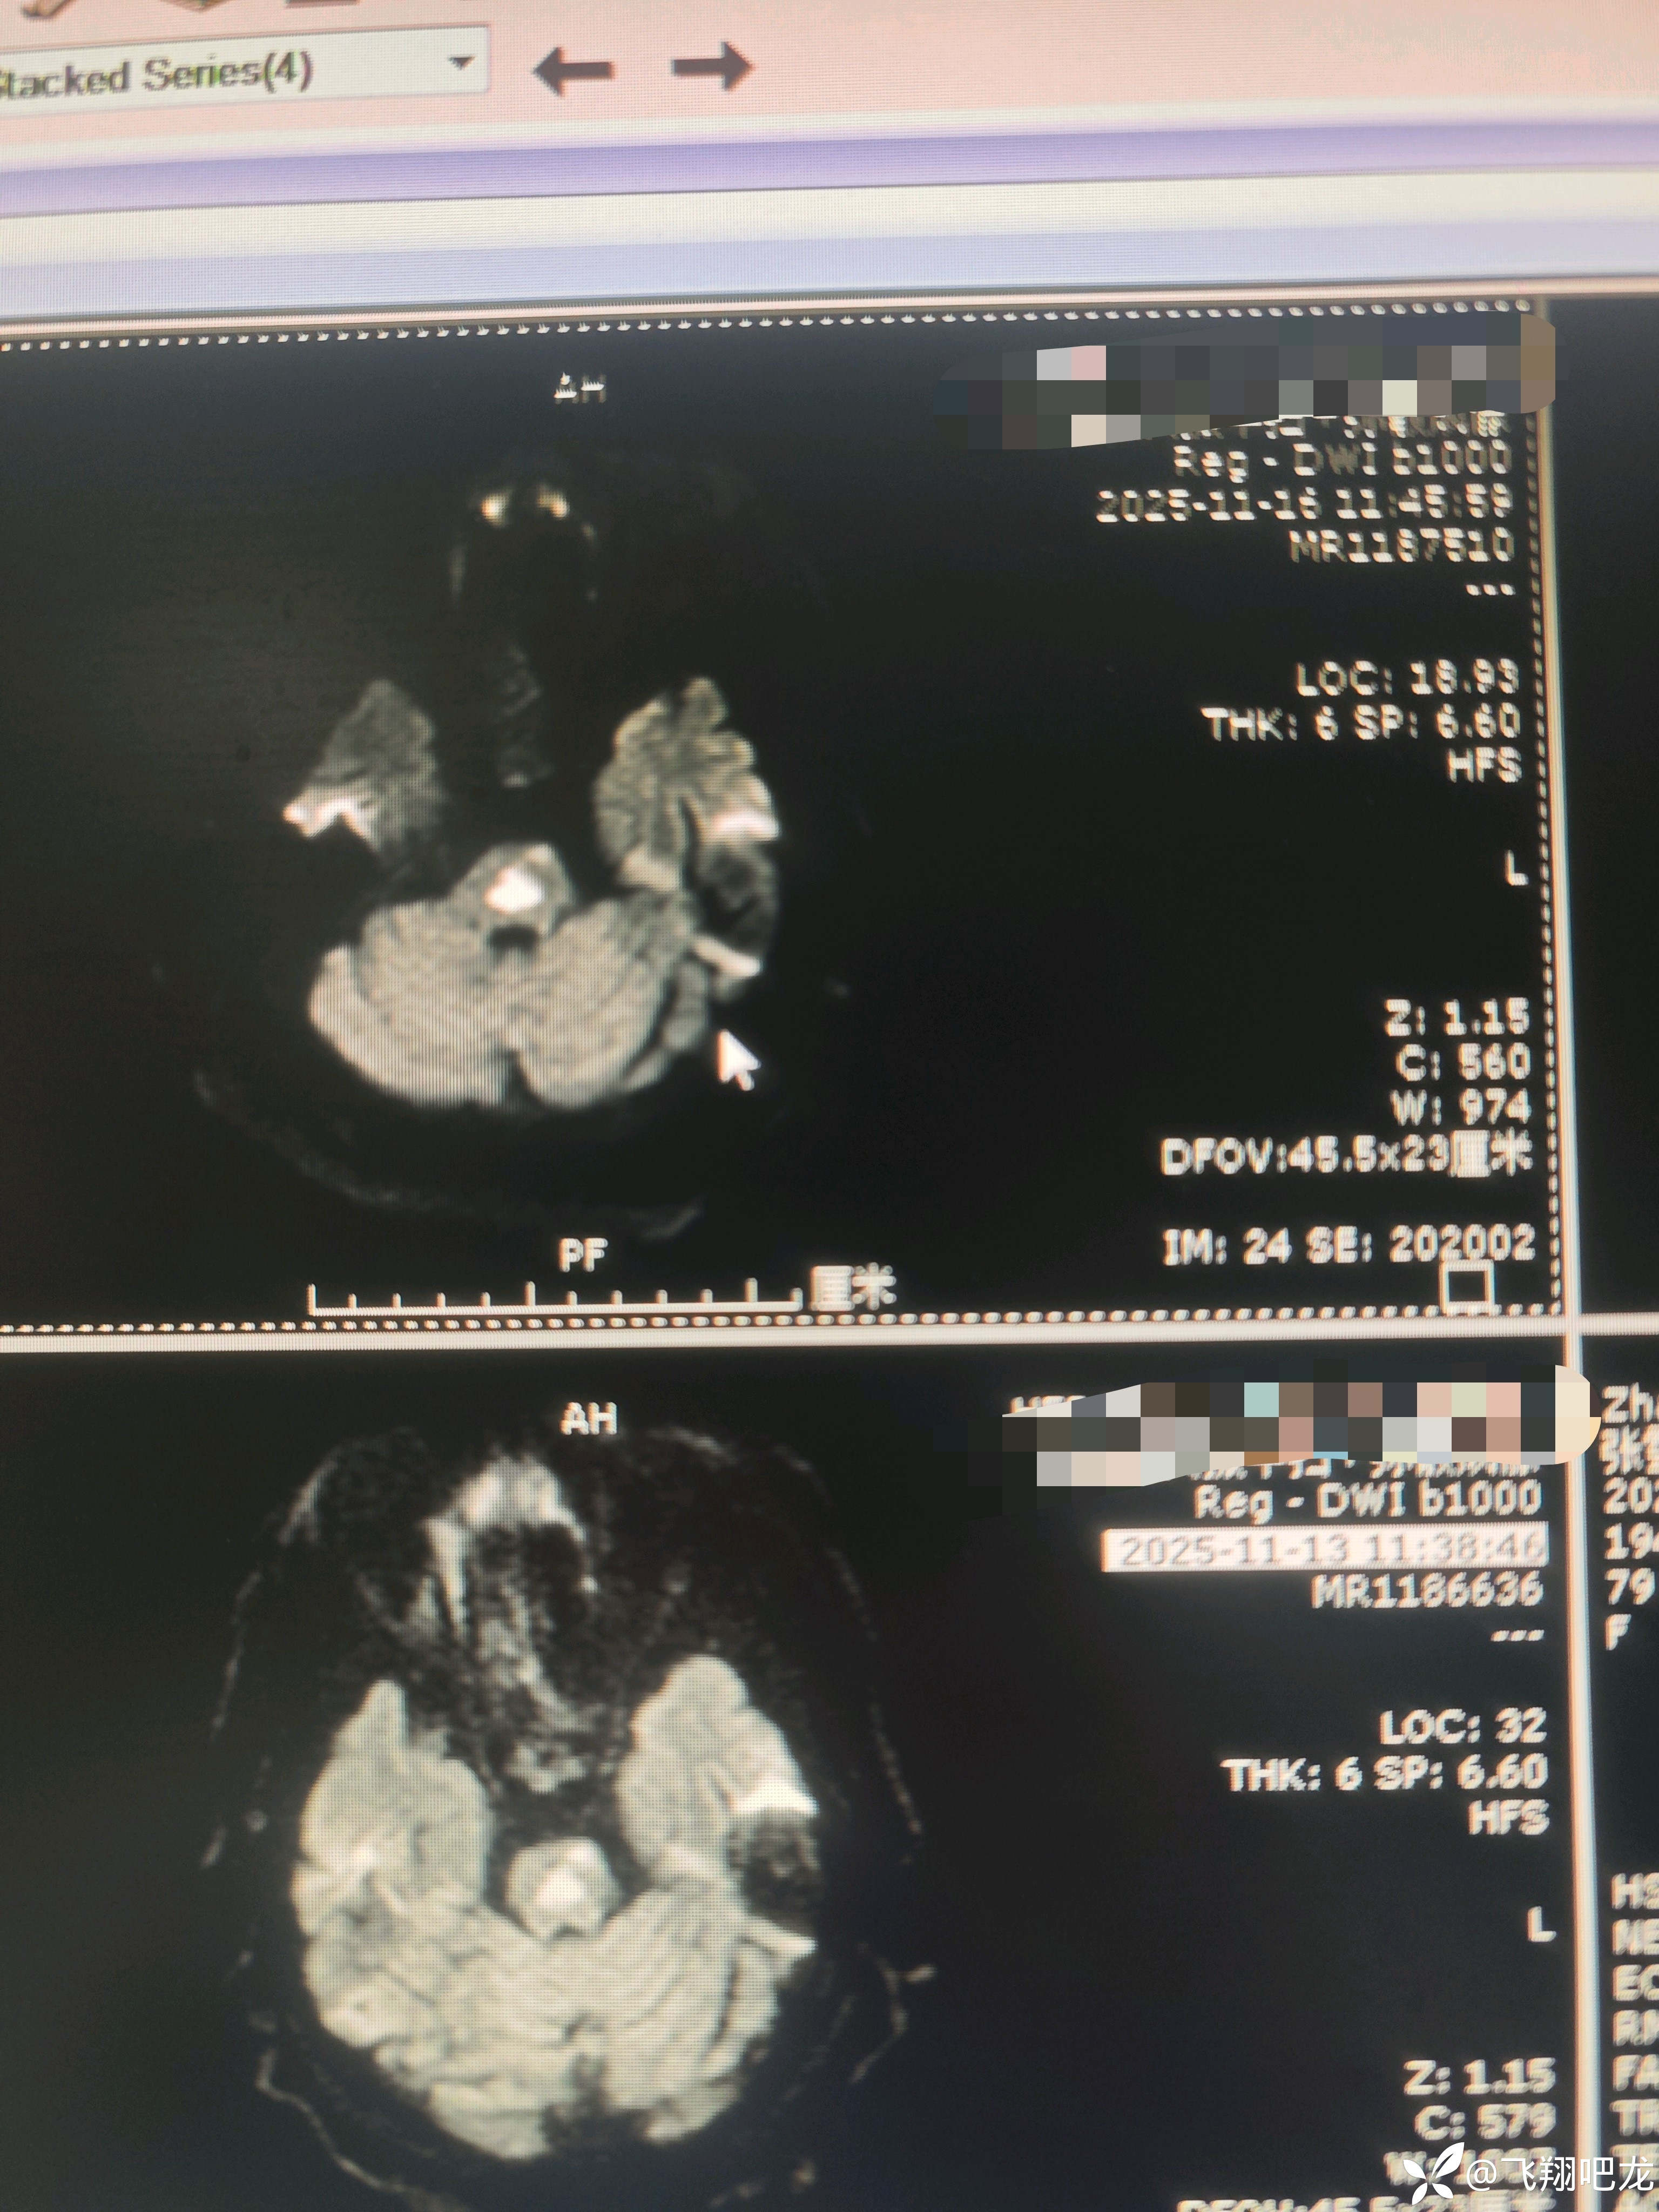

患者老年女性主因是脑梗死住院,入院后治疗期间再发意识不清。查核磁梗死面积加重。